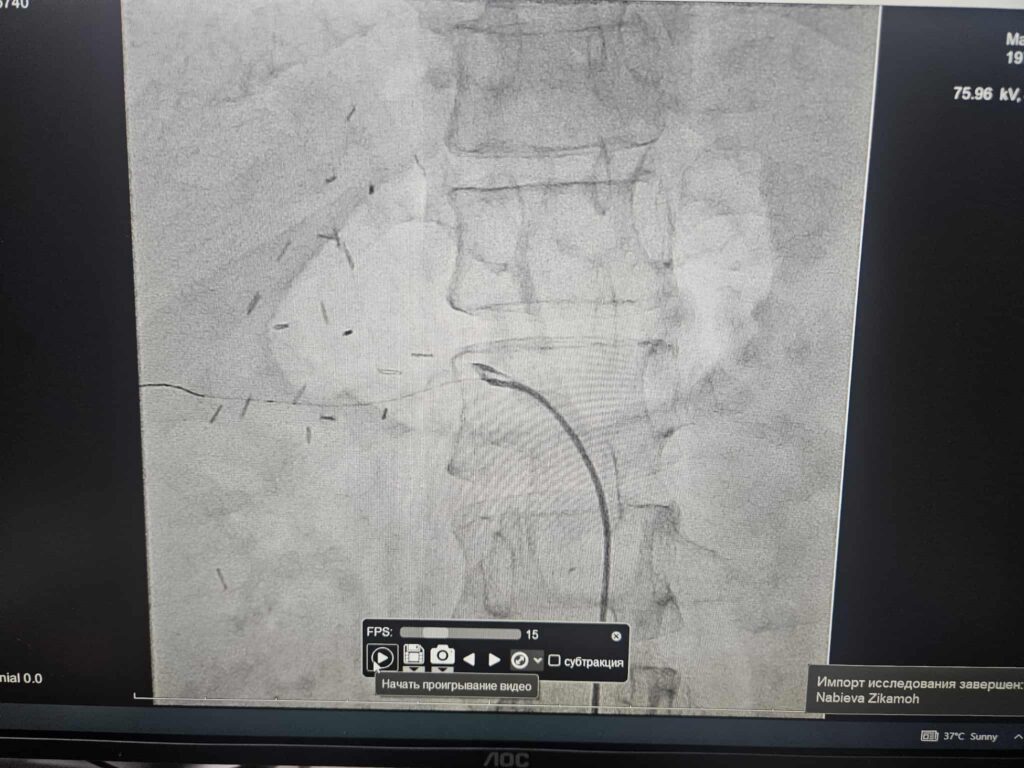

Ҳамин тавр, татқиқоти дастгоҳи муосири ангиография нишон дод, ки бемор дорои синдром, яъне ҳолате, ки дар он шараёни испурчи калоншуда қисми зиёди хунро ба худ ҷалб мекунад ва ба таъминоти муътадили хун ба ҷигар халал мерасонад, мебошад.

Пас аз баррасии машварат мутахассисони ин марказ ба қарор омаданд, ки ба бемор эмболизатсияи шараёни испурч гузаронида шавад. Хушбахтона, қисмати дисталии раги испурчи калоншуда бо эмболҳои сферикии андозаи 900–1200 мкм бомуваффақият баста шуд.

Гузаронидани ангиографияи такрорӣ пурра барқарор шудани гардиши хун дар раги шараёни беморро нишон дод, ки он самаранокии усулро тасдиқ намуда, ба устувор шудани вазъи саломатии бемор мусоидат намуд. Ин амалиёт ба бемор бе буриш гузаронида шуд.